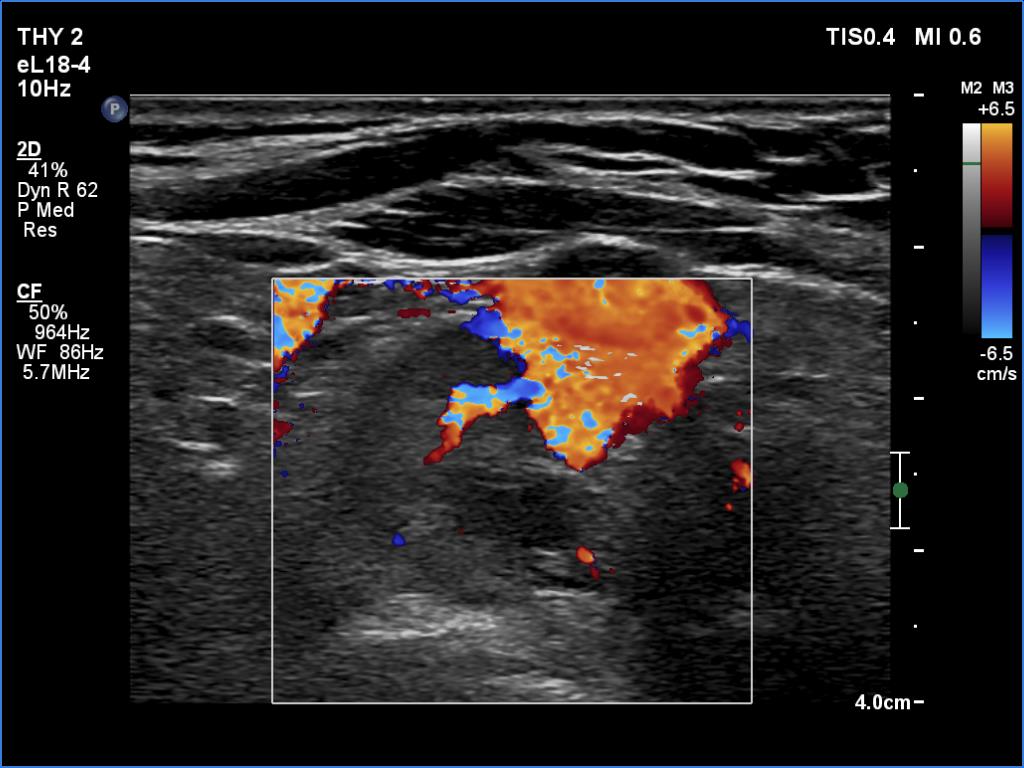

Second examination 6 month later (2nd row of images)

Clinical presentation. The patient was referred for evaluation of hyperparathyroidism. Elevated calcium and parathyroid hormone levels were found during the first evaluation. (These findings were not yet available when I first examined the patient.) Further evaluation disclosed a hyperfunctioning right lower parathyroid. The patient was operated on but no parathyroid tissue was found on histopathology. (A more experienced parathyroid surgeon was quarantined at the scheduled time of the operation, so a less experienced colleague performed the surgery.) Both hypercalcemia and hyperparathyroidism have persisted.

Laboratory tests: parathormone 129 pg/ml (normal value: 12-88), serum calcium 2,89 mM/L, phosphate 0,71 mM/L.

Ultrasonography revealed a hypoechoic mass corresponding to the right lower parathyroid.

Cytology resulted in benign lesion, a pattern which corresponded to a parathyroid adenoma.